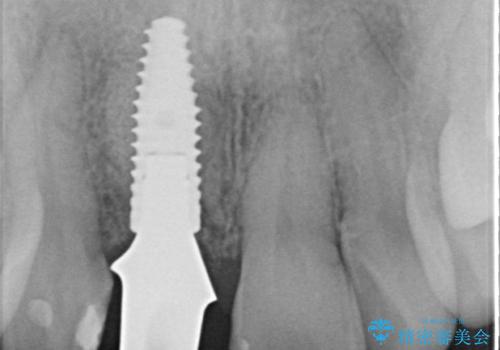

骨造成を伴う前歯のインプラント治療

審美的・機能的に良好な位置に埋入するには、骨量が十分ではなかったため骨の造成を併用したインプラント埋入外科手術を行います。

前歯のインプラントを審美的に仕上げるには、インプラント周囲に十分な骨の量と厚みのある歯肉、そして埋入位置の精密な位置付けが重要です。